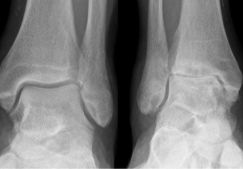

Артриты — группа воспалительных поражений суставов различного происхождения. В патологию постепенно вовлекаются гиалиновые хрящи, связочно-сухожильный аппарат, синовиальные сумки и их оболочки. Артрит может быть инфекционно-аллергическим, травматическим, метаболическим, дегенеративно-дистрофическим, реактивным. Многие виды заболевания пока не поддаются окончательному излечению, несмотря на использование самых современных фармакологических препаратов. Терапия направлена на снижение выраженности симптоматики, предупреждения распространения воспаления и деструктивных изменений на здоровые ткани.